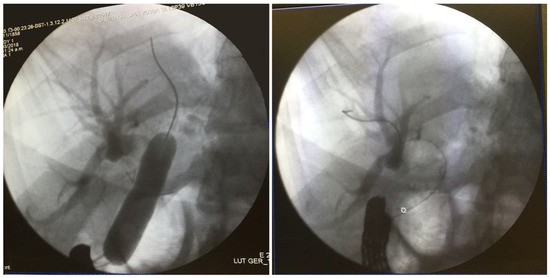

Transjejunal Laparoscopic Assisted ERCP in a Patient with Roux-en-Y Hepaticojejunostomy

2. Case Presentation